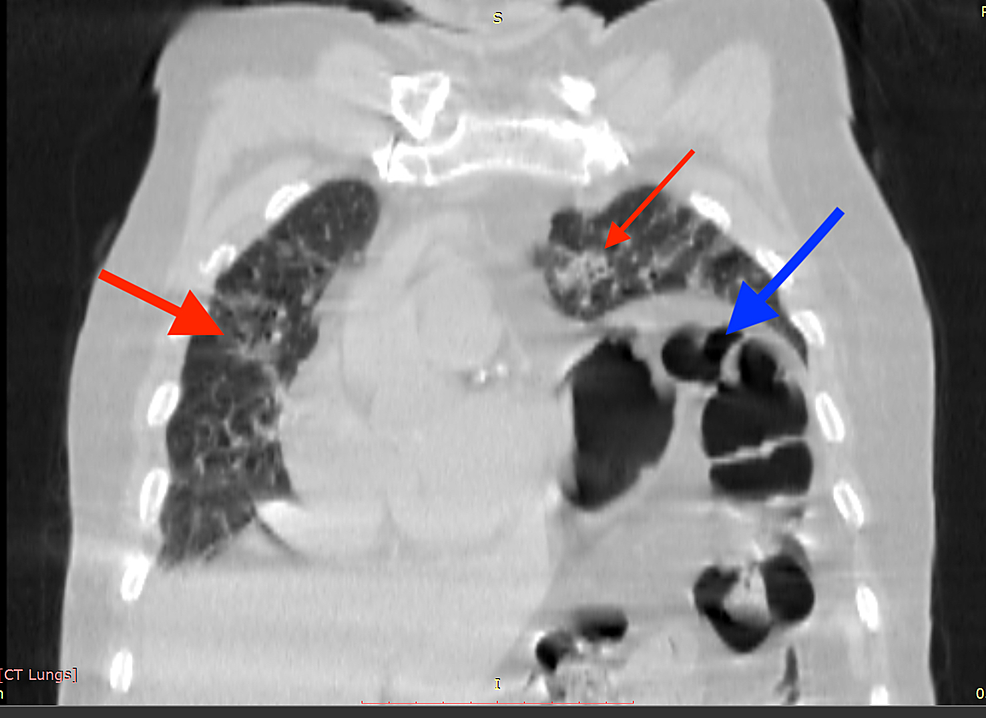

Diaphragmatic excursion. Coronal images of (a) full inspiration and (b Diaphragmatic Excursion In Pneumonia diaphragmatic excursion is the movement of the thoracic diaphragm during breathing. this study aimed to assess the impact of diaphragmatic excursion (dex) measured by ultrasound on the prognosis. the function of the diaphragm can be evaluated at the bedside by measuring diaphragmatic excursion using. diaphragmatic excursion is positively correlated with lung inspiratory. Diaphragmatic excursion showed an. Diaphragmatic Excursion In Pneumonia.